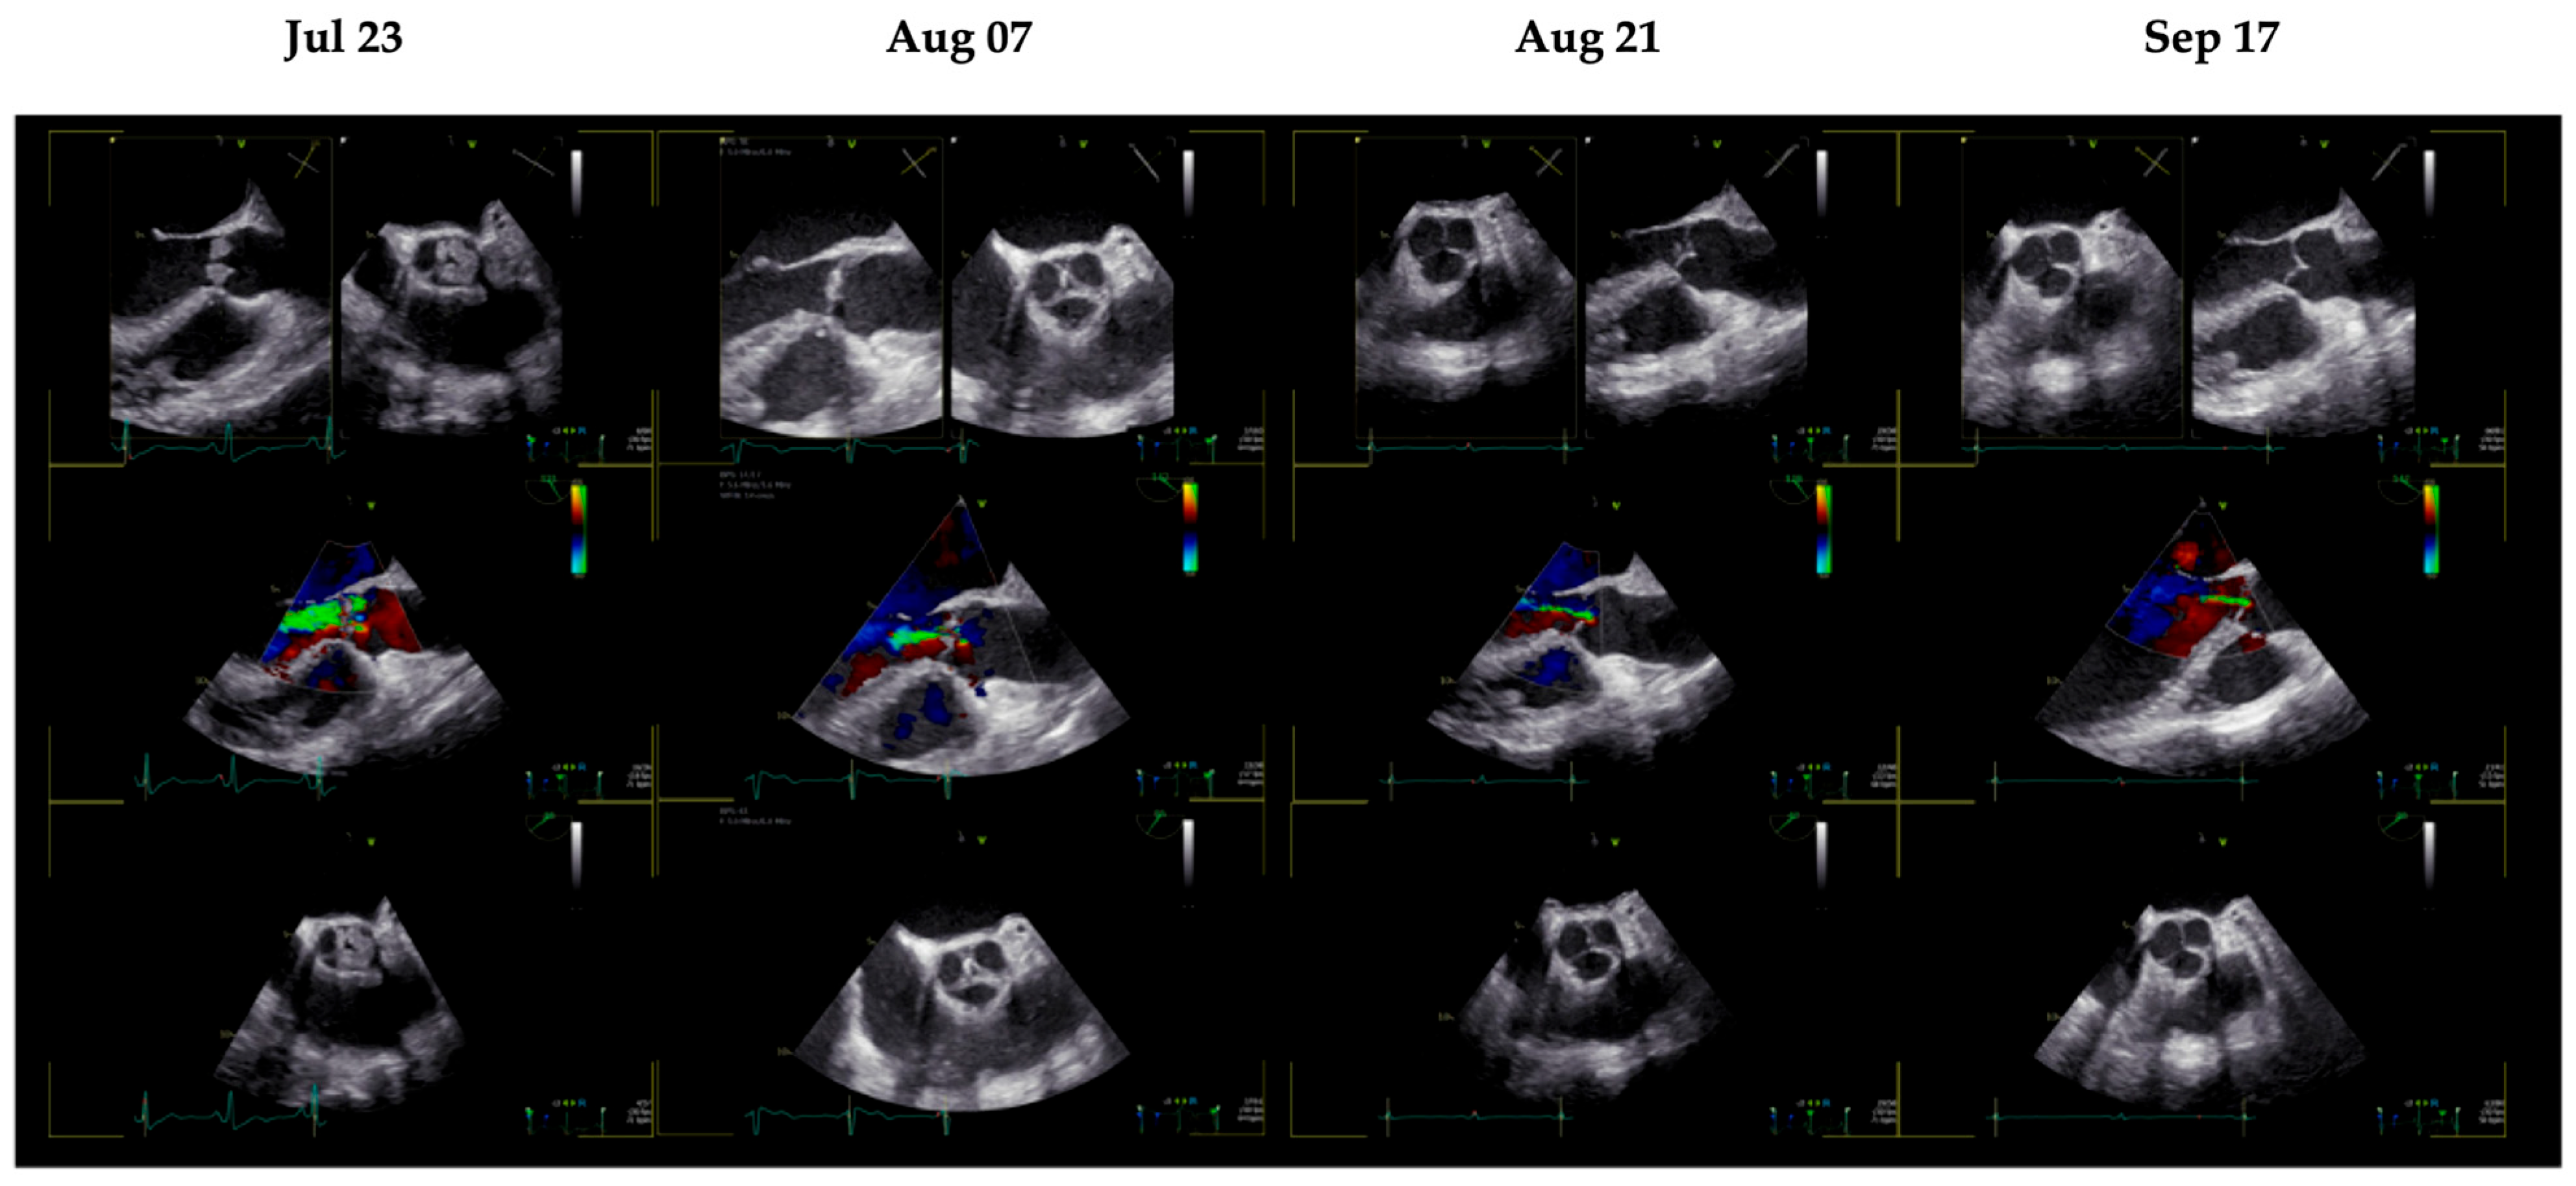

| 23 July 2025 | TEE | Diagnosis of NBTE under DOAC therapy |

| 30 July 2025 | TEE | Echocardiographic NBTE unchanged |

| 7 August 2025 | TEE | Partial regression of aortic valve vegetations |

| 21 August 2025 | TEE | Single residual vegetation on the right coronary cusp |

| 17 September 2025 | TEE | Complete resolution of aortic valve vegetations |

| 21 October 2025 | TEE | Persistent absence of vegetations |

| 18 December 2025 | TEE | Persistent absence of vegetations |